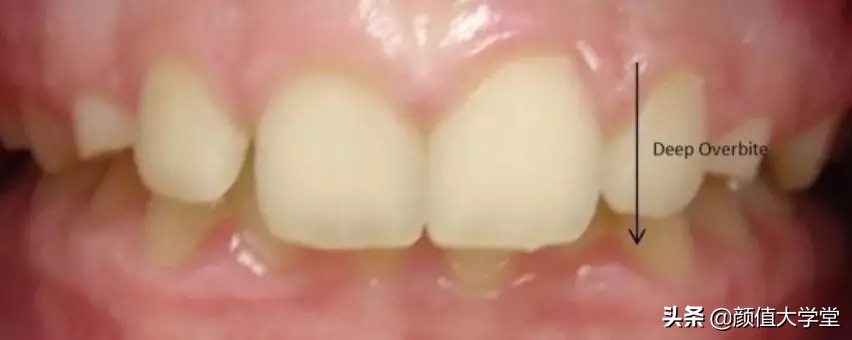

2、深覆合

像下面这样,在牙齿闭合时,上牙把下牙给盖住,下牙只是露出很少一部分就是深覆合。如果有深覆合的情况,要么是因为上牙槽骨发育过度,要么是下牙槽骨发育不足导致的。

深覆合会导致我们的下巴从正面看起来很短,侧面后缩。这种情况的改善方法比较简单常见,也就是去做正畸,不过得花个1~2年的时间(如果骨性问题也突出,可以联合正颌手术矫正)。